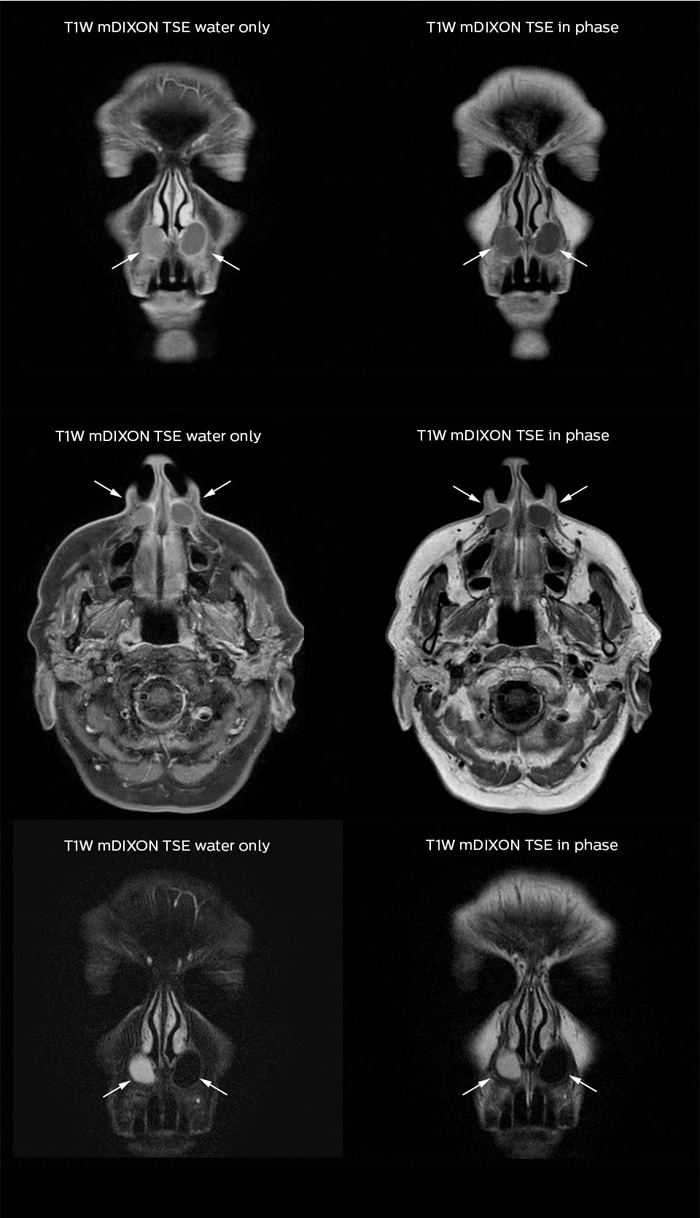

Mri and Ct Atlas of Correlative Imaging in Otolaryngology

Mri and Ct Atlas of Correlative Imaging in Otolaryngology,

Mri and Ct Atlas of Correlative Imaging in Otolaryngology, Mri And Ct Atlas Of Correlative Imaging In Otolaryngology,

Mri And Ct Atlas Of Correlative Imaging In Otolaryngology, CT & MRI Pathology: A Pocket Atlas: 9780071380409: Medicine,

CT & MRI Pathology: A Pocket Atlas: 9780071380409: Medicine, Pocket Atlas of Head and Neck MRI Anatomy: Lufkin, Robert B,

Pocket Atlas of Head and Neck MRI Anatomy: Lufkin, Robert B, Axial CT scan of the atlas immediately after trauma (A) and,

Axial CT scan of the atlas immediately after trauma (A) and, Diagnostic Imaging: Musculoskeletal Non-Traumatic Disease,

Diagnostic Imaging: Musculoskeletal Non-Traumatic Disease, Cranial Neuroimaging and Clinical Neuroanatomy: Atlas of MR,

Cranial Neuroimaging and Clinical Neuroanatomy: Atlas of MR, CT & MRI Pathology: A Pocket Atlas, Second Edition,

CT & MRI Pathology: A Pocket Atlas, Second Edition, Diagnostic Imaging of the Head and Neck: MRI with CT & PET,

Diagnostic Imaging of the Head and Neck: MRI with CT & PET, MRI Atlas of the Human Cerebellum - 1st Edition | Elsevier Shop,

MRI Atlas of the Human Cerebellum - 1st Edition | Elsevier Shop, Raise the standard in MRI - FieldStrength MRI | Philips,